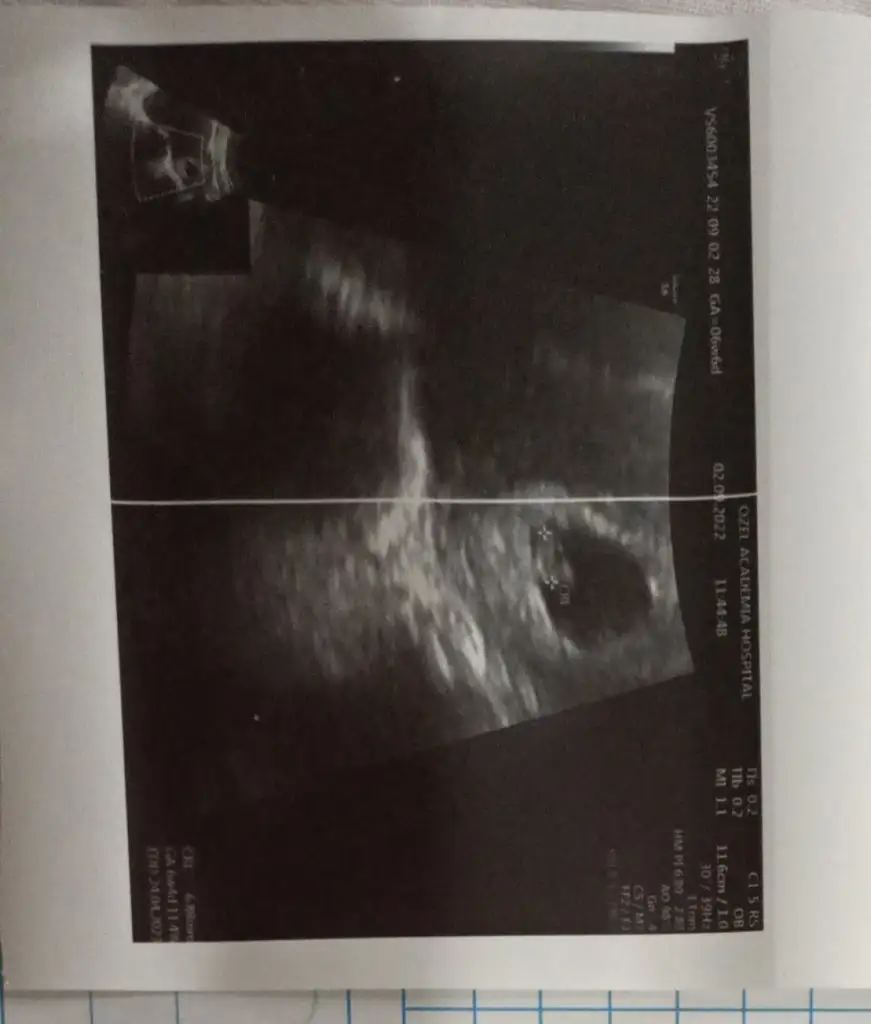

Kızlarr bu da benim ultrasonum kesenin sağı solu mu benim sağım solum mu onu anlamadığım için bilirkişi olarak size sorayım dedim. Acaba bizim vatandaşın cinsiyeti ne ramziye göre?

Eklentiler

• IMG_20220911_192021.webp

IMG_20220911_192021.webp

17,3 KB · Görüntüleme: 67

Anaam teorilere kapali demek 😂 benimki tam solda tünemişti en son gordugumde 😂

Evet benimki üstümden teoriler kurmayın şeklinde duruyordu😂